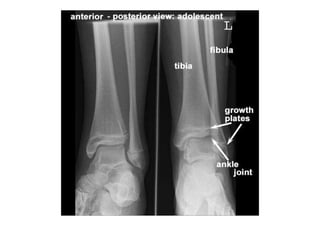

RADIOLOGIA DO

TRAUMA DO ESQUELETO

Referência: http://www.accessexcellence.org/RC/VL/

figura